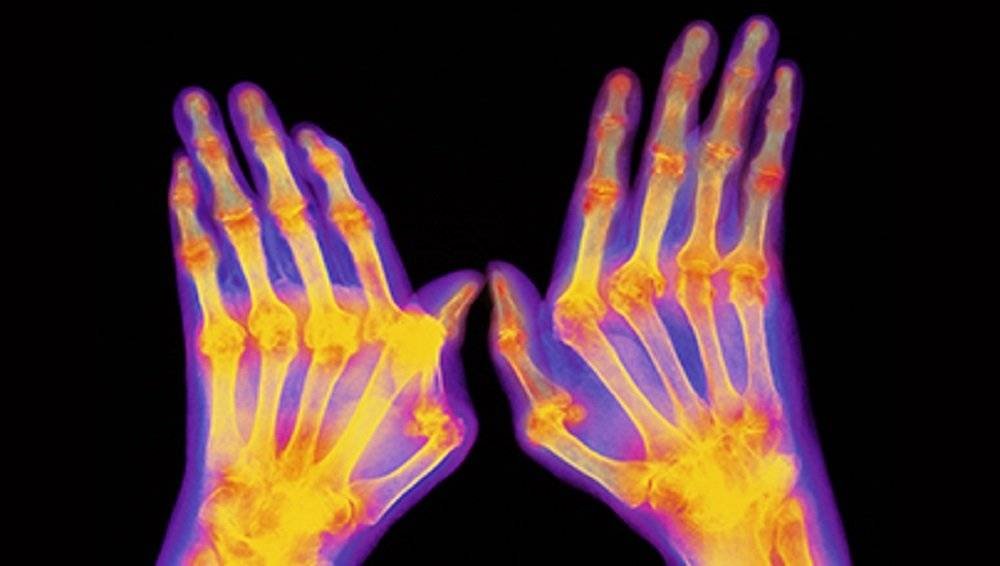

Of the most common complaints and symptoms that occur when it comes to arthritis, pain, stiffness and swelling of the joints is the top of the list. The pain occurs in a variety of places but the most regularly affected areas are the feet, wrists, fingers, ankles, hips and spine amongst others.

On the other hand, Rheumatoid arthritis is a disorder that results in systemic inflammation affecting the joint, and in certain circumstances, affecting other tissues and organs that surround the joint. It causes swelling and an inflammation of the capsule that surrounds the joint, resulting in fibrous tissue developing and an excess synovial fluid within the joint capsule. In the long term, this can result in the destruction of the joints cartilage or even fusion of the joints.

Rheumatoid arthritis can sometimes result in an inflammation of the lungs, the membranes around the heart, the whites of the eyes and the membranes of the lungs. While it’s considered to be a systemic Autoimmune Disease, the exact cause of Rheumatoid arthritis is still unknown.